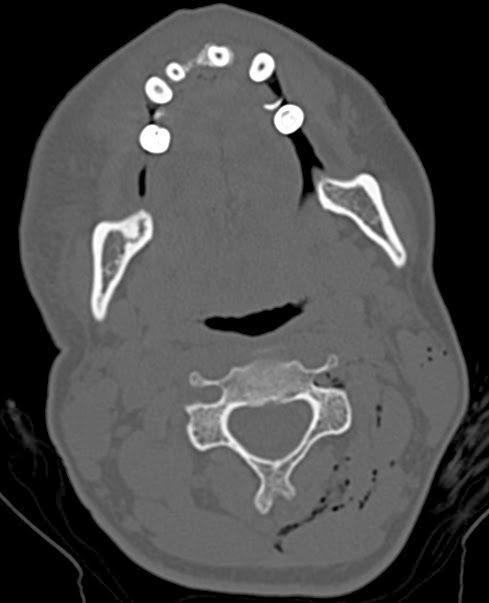

Szerző: admin | jan 6, 2014 | Trauma, WTF

gas bubbles in the soft tissues of the neck and the vertebral canal (left side) Young girl stabbed herself on the neck with a syringe. She inflated air several times into the soft tissues with suicide intention.1691932013.12.25.Courtesy of Molnár...